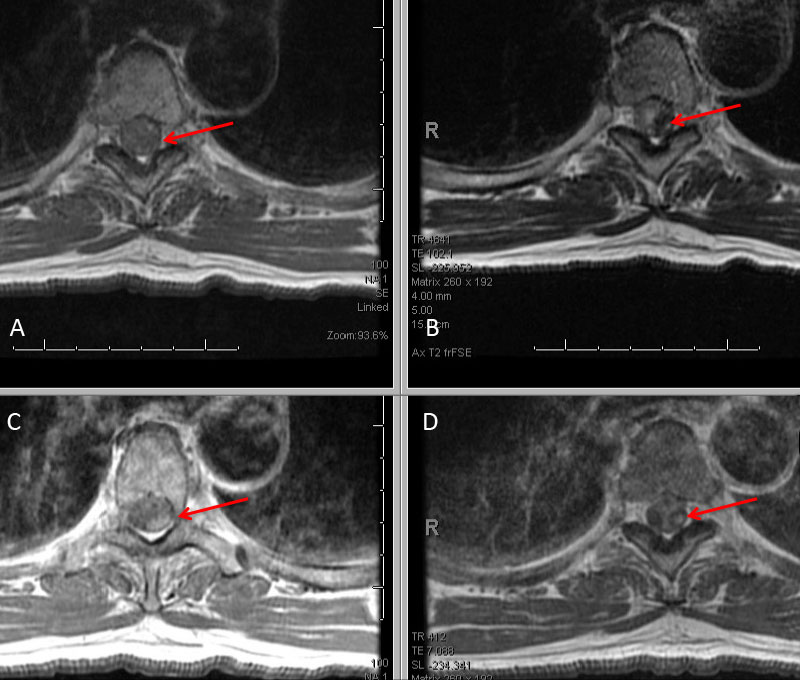

His initial angiogram excluded an underlying aneurysm or high flow arterial venous malformation of the brain, however a dissecting aneurysm of the left T5 pedicle was malformation of the brain, however a dissecting aneurysm of the left T5 pedicle was identified extending into the left T4-T5 left paramedullary space (Figure 3. A).

Figure 3: A) Initial left T5 DSA; B) 5 days post; C) Microcatheter DSA D) Post Coil Embolization demonstrating aneurysm obliteration

A selective WADA test of the left T5 pedicle with Brevital and lidocaine was performed and demonstrated loss of motor and sensory signal on intraoperative monitoring within the left lower extremity suggesting that this dissecting aneurysm of left T5 did have some contribution to the anterior spinal axis at this level. After initial discussions of options, we decided to initially place him on medical therapy with aminocaproic acid (72 hours), bed rest, and hemodynamic control of his blood pressure in the efforts to allow the aneurysm dissection to heal and potentially spontaneously thrombose. In addition, we volume expanded him in efforts to develop collaterals in the event that embolization of this dissection was required. A follow-up angiogram performed 5 days later demonstrated that the dissection did not thrombose and appeared very similar to the initial angiogram (Figure 3. B) and felt to represent a high risk for recurrent hemorrhage. We had extensive discussions with the patient and his spouse, who were prepared for potential difficult decisions regarding treatment of this high-risk lesion. Based on our judgment, we felt that the risks of recurrent hemorrhage were significant and that embolization of the feeding pedicle of left T5 should be performed to decrease the risk of potentially life-threatening or paralyzing disabling hemorrhage. We performed a coil embolization of the left T5 pedicle at the origin of the spinal artery, with the intention that collateral perfusion of the spinal cord would be achieved by adjacent healthy pedicles (Figure 3. C and D). He tolerated the procedure very well without adverse events or new neurologic deficits. We maintained the patient in the neuro ICU on bedrest with permissive hypertension and anticoagulation for 24-48 hours to encourage collateralization. After an additional 2 days of mobilization and observation, and a follow MRI demonstrating improved myelopathic signal and resolving focal left T4 hemorrhage, he was discharged home neurologically intact in good condition. Over the hemorrhage, he was discharged home neurologically intact in good condition. Over the next 6 weeks, his symptoms of abdominal and back pain resolved, and he regained all of his activities of daily living without limitation or neurologic deficits.